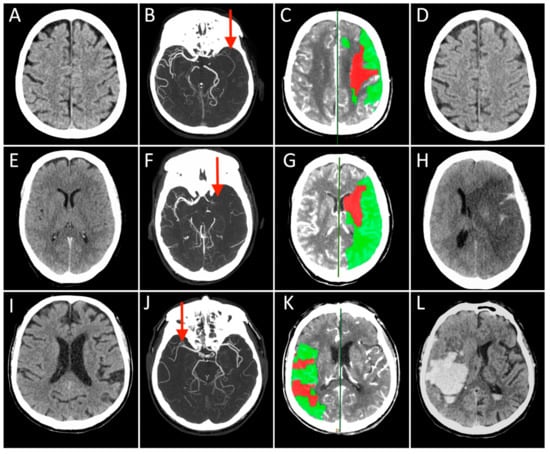

Case 1: A 73-year-old man with a history of hypertension, dyslipidemia, and prior myocardial infarction presented to the emergency department after the sudden onset of right-sided weakness and difficulty speaking. NCCT showed early ischemic changes in the left insular territory with an ASPECT score of 9 (Figure 1A). The mCTA demonstrated occlusion of the distal left M1 segment of the middle cerebral artery (MCA) with good collateral circulation (Figure 1B). A large penumbra in the left MCA territory with CBV lesion volume ≤ 50% of MTT lesion size (Figure 1C). After IVT, started 115 min after symptom onset, he underwent MT with complete recanalization (onset to recanalization time 280 min). In the 24 h follow-up CT scan, no ischemic lesion was visible (Figure 1D), and the patient experienced a great clinical improvement over the subsequent 3 days. At the 3-months follow-up, the patient was functionally independent.

Each row represents a single patient’s images derived in different modalities and timepoints (Case 1 presented in (A–D), Case 2 in (E–H), and Case 3 in (I–L)). The first three columns on the left show the Non-Contrast-CT (NCCT), multiphase CT Angiography (CTA), and CT Perfusion (CTP) performed at hospital arrival, while the last column on the right displays the NCCT acquired at 24 h after stroke. On presenting NCCT (A,E,I) no early ischemic changes can be seen in the brain tissue in Case 2 and 3 (ASPECT score = 10), while a tissue swelling was detected in the right insular lobe in Case 1 (ASPECT score = 9, not shown). The mCTA images identified proximal (M1 segment) Middle Cerebral Artery (MCA) occlusion in the left hemisphere in (B,F), and contralateral side in (J) (red arrows). CTP showed in all cases a small infarct core corresponding to CBV lesion (red) and a large ischemic penumbra consisting of the difference between MTT and CBV lesions (green), representing the expected “salvageable” tissue after recanalization. In these patients, CBV lesion volume ≤ 50% of MTT lesion size. All patients were treated with combined IVT and MT, obtaining a complete recanalization, but the 24 h NCCT showed three different conditions: no ischemic lesion visible (D), complete MCA territory infarct associated with a massive cerebral oedema (H), and a vast hemorrhagic transformation of the ischemic lesion.

Case 2: A 71-year-old woman presented to a local emergency department 1 h after the sudden onset of speech difficulties and hemiparesis involving the right face, arm, and leg. She had a history of poorly controlled cardiovascular risk factors. NCCT showed a left MCA hyperdense sign (Figure 1E). The mCTA demonstrated a proximal left MCA occlusion (Figure 1F). CTP revealed a large penumbra in the left MCA territory with CBV lesion volume ≤ 50% of MTT lesion size (Figure 1G). She had no contraindications for IVT that was started 160 min after symptom onset. The patient then underwent endovascular treatment with complete recanalization that was not followed by clinical recovery (onset to recanalization time 300 min). Serial NCCT scans demonstrated progressive edema with mass effect in the left MCA distribution and 12 mm of midline shift (Figure 1H). She required endotracheal intubation and was admitted to the neurocritical care unit. The patient died the next day.

Case 3: A 70-year-old man had a sudden onset of left hemiplegia and forced eye deviation to the right. His medical comorbidities included hypertension, dyslipidemia, type 2 diabetes mellitus, and coronary artery disease. On neurological examination, he was awake, unable to communicate or follow commands. He had forced right gaze deviation, left hemianopsia, moderate left arm and leg weakness. NCCT identified hyperdense right MCA sign. The ASPECT score was 10 (Figure 1I). The mCTA showed an occlusion of the right proximal M2 segment of the MCA with a good collateral flow (Figure 1J). CTP demonstrated a large penumbra in the right MCA territory with CBV lesion volume ≤ 50% of MTT lesion size (Figure 1K). He received IVT after 90 min from clinical onset and underwent MT with complete recanalization (onset to recanalization time 215 min). The patient showed initial mild clinical improvement that was followed by both a rapid deterioration of consciousness and worsening neurological conditions with extensor posturing. Follow-up NCCT demonstrated an evolving infarct of the right MCA territory with hemorrhagic transformation and 8-mm midline shift (Figure 1L). He underwent surgical hematoma drainage with partial improvement. The patient was unable to walk and dependent on daily activities at the 3-month follow-up.